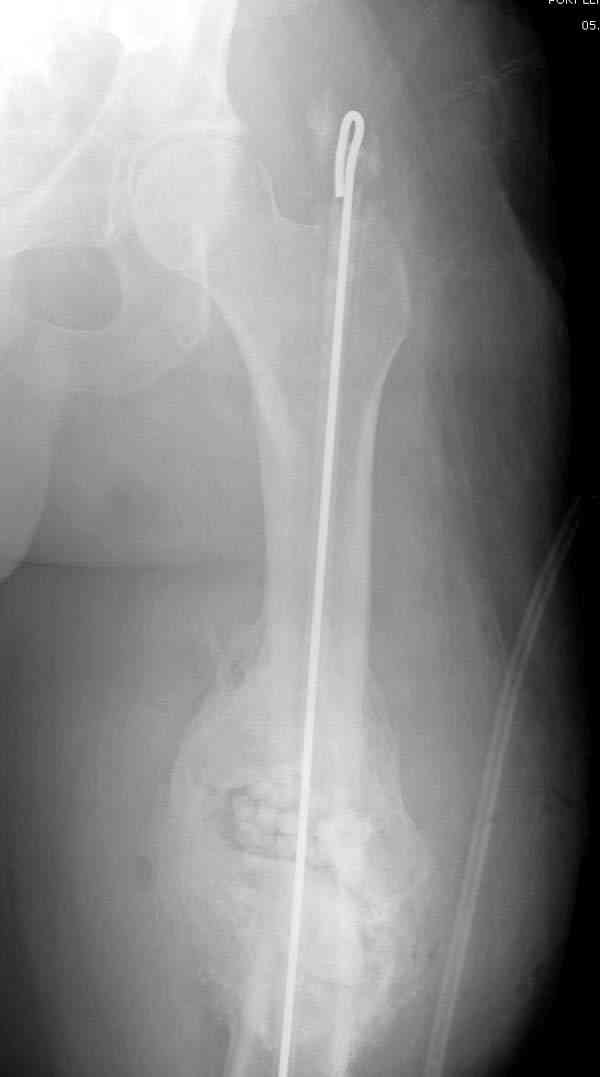

После нескольких некрэктомий, проведения аутодермопластики и заживдения ожоговой раны через 2 месяца после травмы произведен открытый остеосинтез левой бедренной кости штифтом и пластиной (деротационной) [image 01, 02]. Через 1 год и 7 месяцев после травмы у больного диагностированы ложный сустав и хронический остеомиелит левой бедренной кости. Произведено удаление металлических фиксаторов, секвестрэктомия и остеосинтез бедренной костивнешним двухплоскостным стержневым аппаратом [image 03, 04] .